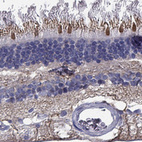

Immunohistochemical staining of human retina shows strong cytoplasmic positivity in cones and nerve fibers.